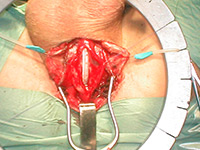

Буккальная 1 этапная уретропластика – Фотогалерея